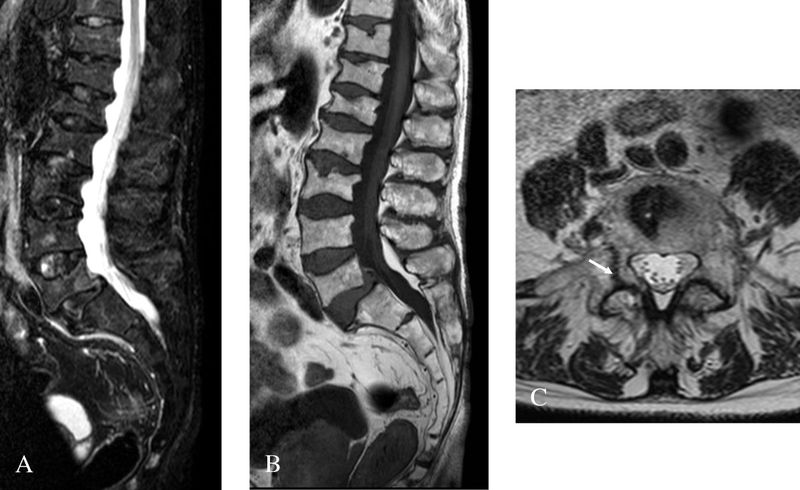

(Bild: Dr. Robert Carlier - Eigenes Werk, CC BY 2.0, https://de.wikipedia.org/wiki/Morbus_Fabry#/media/File:Morbus_Fabry_MRT_Osteoporosis_01.jpg) (Bild: Dr. Robert Carlier)